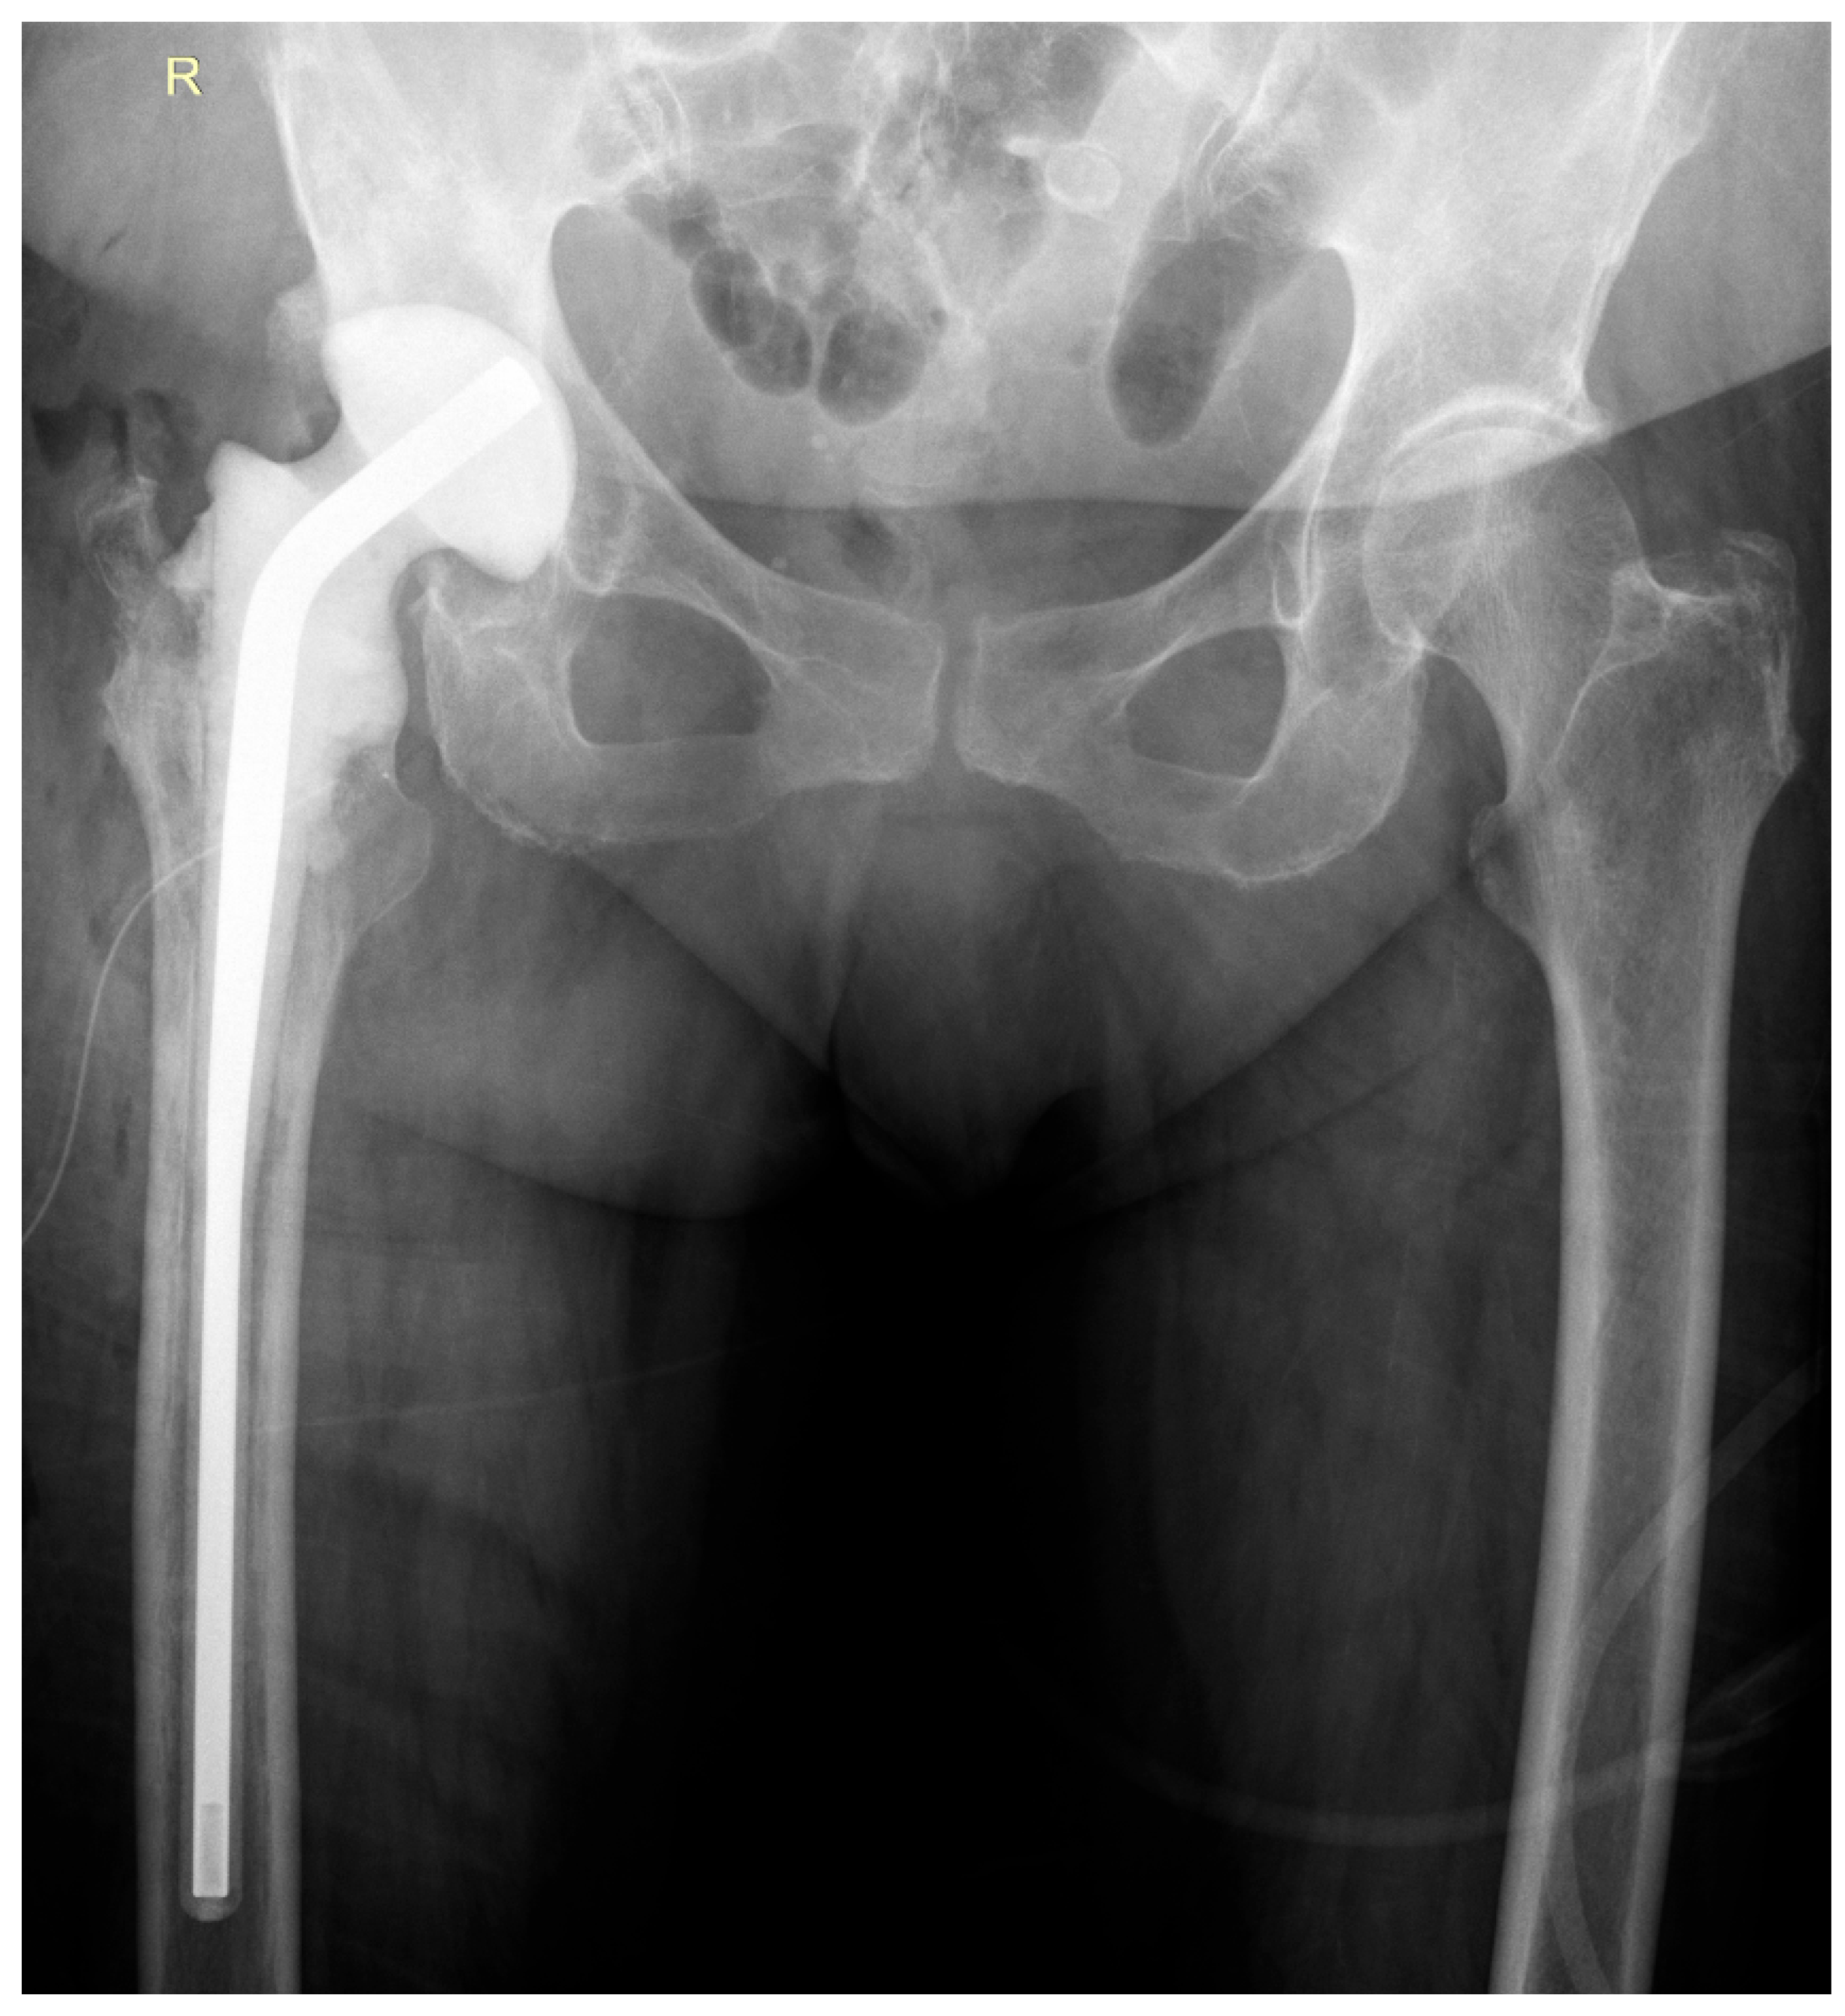

2. Case Report